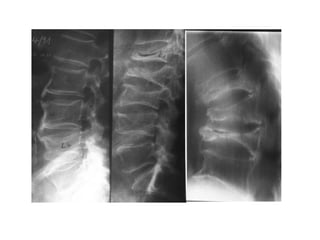

X - Ray

• Absolutely required

• Even if bone mineral density informs us about

bone content, it does not show the fracture or it

can reveal the bone better than it is, because of

degenerative changes

Semiquantitative assessment of vertebral

fractures

SQ stage

0 normal

1 mild

2 moderate

3 severe

Genant et al. J BoneGenant et al. 1993: 8;Mineral Res 1993: 8; 1137-48

Mineral Res J Bone 1137-48